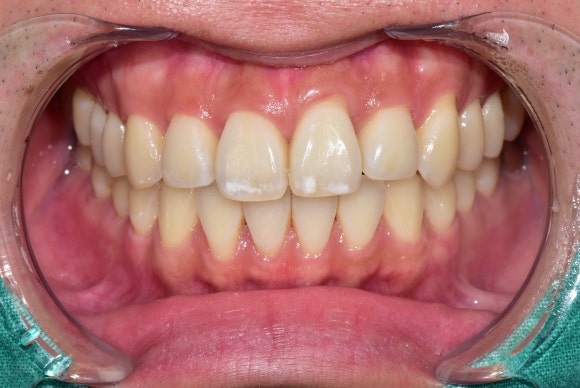

가지런한 치아와 환한 미소가 아름다운

20대 남성 환자분이 오셨습니다.

치아 끝에 두드러지는 흰 색 반점을 없애고 싶다고 하셨습니다.

20250211

다시 우리 환자분으로 돌아와서....

1회 시술하는 데 15~20분 밖에 걸리지 않습니다.

치료해야 할 치아가 여러 개더라도

동시에 진행하면 되기 때문에 문제가 되지 않습니다.

흰색 반점의 범위가 너무 넓은 경우

1회 시술로 불충분할 수 있습니다.

필요한 곳은 1회 시술을 더 추가하면 됩니다.